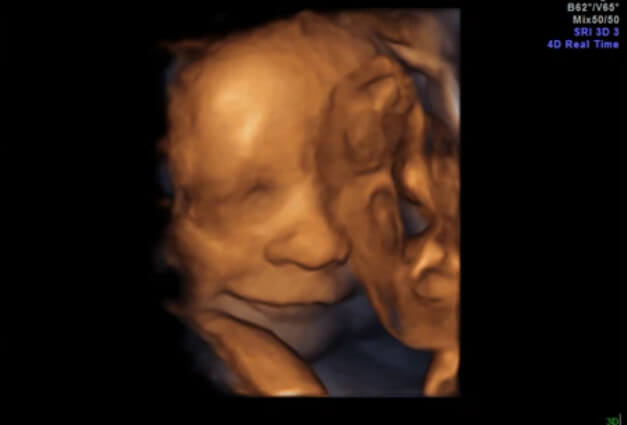

33 Haftalık Bebeğin Ultrason Görüntüsü

• 33. haftadan sonra, vajinal kanama ya da çok sık ve uzun süren braxton hicks kasılmaları olması nedeniyle, doktorunuz ultrason kontrolü sayınızı arttırmış olabilir. Ancak bu durum her zaman kötüye işaret değildir ve endişelenmenizi gerektirmez; doktorunuz durumunuzu ne kadar yakından takip ederse o kadar sağlıklı bir hamilelik geçirirsiniz.

• 33 hafta gebelik döneminde bebeğinizin ultrasonunda, yüz hatlarını rahatlıkla seçebilirsiniz, hatta gözlerini kapatıp açtığını görmeniz bile mümkün.

• Birçok ebeveynin bebeklerin baş aşağı dönme zamanı konusunda kaygıları olduğunun farkındayız; ama 33. hafta gebelikte bebeğinizin baş aşağı dönüp dönmemiş olması henüz önemli değildir.

• Bebeklerin 32 ilâ 38. haftalar arasında baş aşağı dönmesi beklenmektedir. Şimdilik bebeğiniz hangi pozisyonda daha rahatsa o şekilde duruyor olabilir.